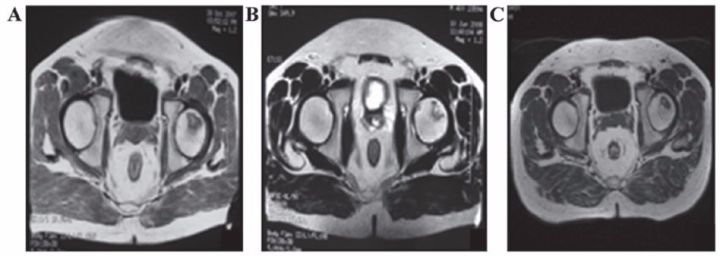

8、泌尿生殖系統(tǒng)疾病

?不孕不育

子宮內(nèi)膜受損嚴重,是很多不孕不育女性的噩夢。現(xiàn)在通過間充質(zhì)干細胞再生技術修復子宮內(nèi)膜,可重圓女性的母親夢。

南京鼓樓醫(yī)院婦產(chǎn)科胡婭莉教授團隊與中國科學院遺傳與發(fā)育生物學研究所戴建武教授團隊聯(lián)手,首次在國際上成功研制出膠原支架復合間充質(zhì)干細胞的方法,結合傳統(tǒng)宮腔鏡技術,實現(xiàn)了受損子宮內(nèi)膜的功能性修復,幫助3名患者實現(xiàn)做媽媽的夢想。

江蘇鹽城的胡女士在31歲到34歲時,經(jīng)過三次自然流產(chǎn),因為流產(chǎn)清宮手術,子宮腔嚴重粘連。南京鼓樓醫(yī)院利用間充質(zhì)干細胞8個月修復了她的子宮內(nèi)膜,使她成功懷孕,并于2014年7月17日誕下了國內(nèi)第一位“再生醫(yī)學寶寶”。